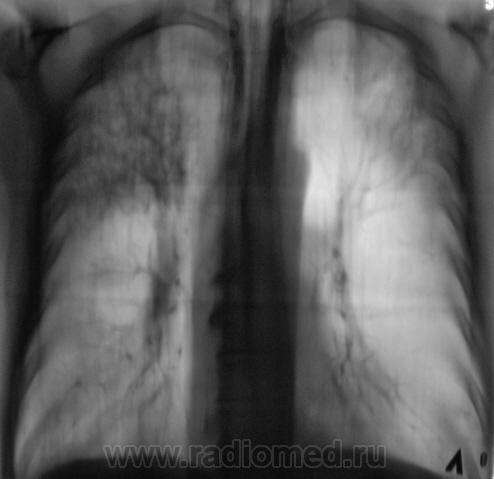

1. Процесс двусторонний.

Вот, и мы так решили, с учетов ограничеснных возможностей нашей ЦРБ-ушки. Взял коллега фтизиатр "изображения", а также и изображения в динамике, а также необходимый "гарнир", и поехал в головное "фтизное" учреждение. В учреждении проконсультировали и выставили правосторонний инфильтративный. Ну и у нас считай - гора с плеч...

Людмила Григолрьевна, но тут, то процесс двусторонний, хоть преимущественно правосторонний. А на полноформатных изображениях (томограммах), и очаги справа в среднем и нижнем легочных полях дифференцировались.

Пациента госпитализировали в областное противотуберкулёзное учреждение. Пролечили в течение месяца.... и выписали.

Произведен контроль после лечения. Заключение рентгенолога данного учреждения - "Со стороны органов грудной полости патологических изменений не выявлено".